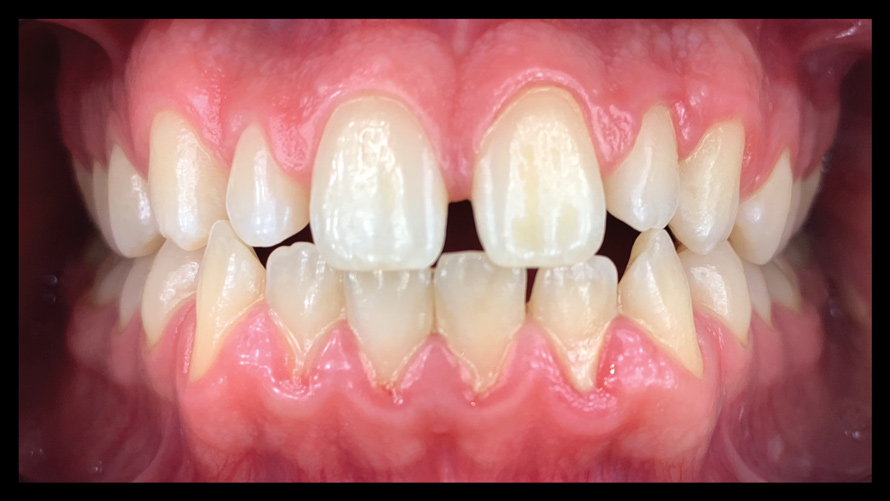

(9.) Preoperative esthetic case documentation using a smartphone and an EALS device.

Figure 9

(10.) Preoperative esthetic case documentation using a smartphone and an EALS device.

Figure 10

(11.) Preoperative esthetic case documentation using a smartphone and an EALS device.

Figure 11